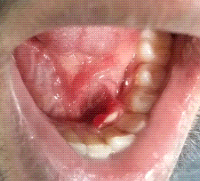

Calcifying Epithelial Odontogenic Cyst of Maxilla: A Clinical and Histological Rarity with Literature Review

Koduri Sridevi, Alpana Talukdar, Saka Malathi, Lavanya Thota, Manisha Patil, Pratyaksha Singh Panwar, Suresh Babu Jandrajupalli, Swarnalatha Chandolu, Abhishek Singh Nayyar

Abstract 400 | PDF Downloads 173 | DOI https://doi.org/10.60787/nmj.v62i1.8

Page 40 - 45

Lymphangioma of Gingiva: A rare case report

Aggarwal Shivani, Varshney Anchal, Aggarwal Ashim, Arora Dimple.

Abstract 354 | PDF Downloads 133 | DOI https://doi.org/10.60787/nmj.v62i1.9

Page 46 - 48